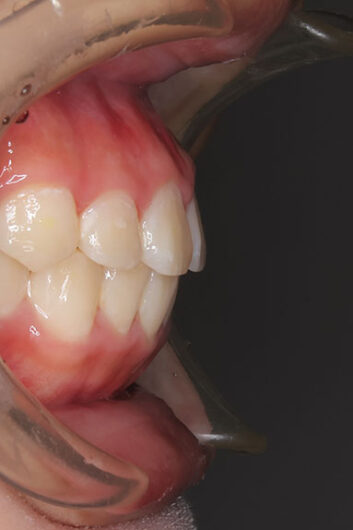

側方歯(犬歯、小臼歯)の生え変わりの時期。 前歯のがたつきを気にされ、小児矯正からの治療を希望されました。 お母様は、矯正治療経験済みですので、治療には前向きで早期治療の必要性を納得されていました。 小児矯正では、永久歯の生え変わるためのスペースを増加させ、がたつきを軽減させることを目的で行います。 残ったがたつきは、全ての永久歯が生え変わってから、本格矯正(マルチブラケット装置での治療)で改善しています。 比較的、叢生量は少ないため、本格矯正は非抜歯にて配列しました。

マルチブラケット 動的治療期間 2年6か月 調整回数16回 特に問題もなく、保定後も安定しています。